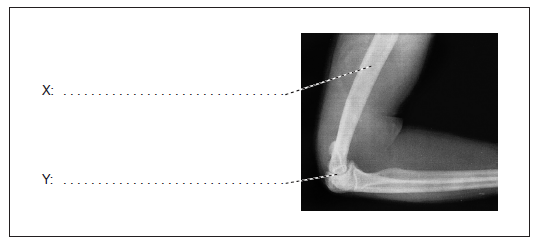

Label the structures indicated on the X-ray of a human elbow.

X: humerus;

Y: synovial fluid / cartilage / joint capsule / elbow joint;